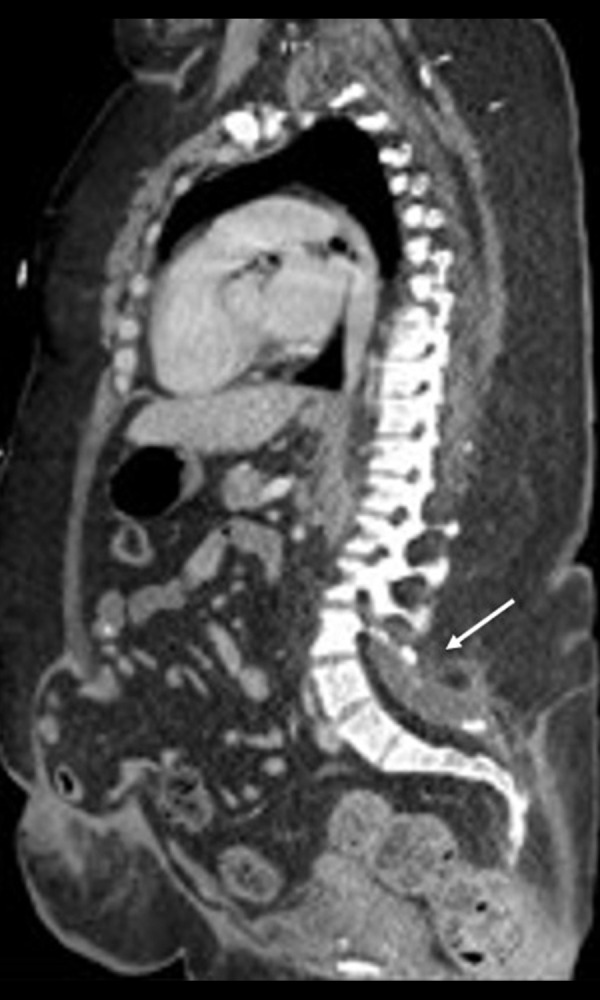

She received 2 units of packed red blood cells in the ED and was admitted to the hospital. Her hemoglobin initially increased to 7.4 g/dL, then dropped to 6.6 g/dL the following day. She did not report any signs of gastrointestinal bleeding, and a stool hemoccult test was negative on admission. A computed tomography scan of the chest/abdomen/pelvis (Figure 2) did not reveal any signs of hematoma or adenopathy and demonstrated normal thymus and spleen. A few days into the hospitalization, she reported blood in her stool, and a repeat hemoccult test was positive. She underwent bidirectional endoscopy with no evidence of active bleeding but with evidence of hemorrhoids. Her transient blood in her stool was suspected to be secondary to hemorrhoids and not likely a significant cause of her hemoglobin change or presentation. She required a total of 5 units of packed red blood cells over a 2-week period before maintaining a stable hemoglobin level for discharge. The cause of acute change in hemoglobin was not identified and did not reoccur, and no additional endoscopies were completed, but she was scheduled to have outpatient gastroenterology at follow-up. The Hematology Department was consulted during her hospitalization regarding her abnormal bone marrow biopsy and elevated ADA level. Parvovirus B19 IgG testing was positive; however, subsequent quantitative viral polymerase chain reaction testing was negative. A transthoracic echocardiogram demonstrated normal structure and function. Her constellation of congenital abnormalities and elevated ADA level led to consideration for a diagnosis of non-classical DBA. Genetic testing subsequently revealed a pathogenic variant in RPL11 c. 158-2_158-1 del AG ins CC, consistent with DBA. Following discharge, she required outpatient packed red blood cell transfusions every other week and iron chelation. Steroids were started after genetic testing identified DBA, but there was no clinical respond and these were discontinued. She has been referred to tertiary care and, at the time of this report, she is under evaluation for an allogeneic bone marrow transplantation.

Figure 2.

Sagittal computed tomography image identifying no intra-abdominal bleeding, chronic spina bifida occulta (arrow), and chronic ventral hernia.